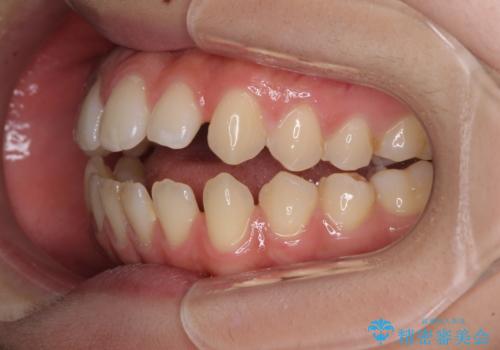

- 上下前歯の隙間と咬み合わない前歯を気にして来院された患者様です。

仕上がりとしては、もう少し上下前歯を接触させたかったのですが、ここまで改善されたことで患者様は大変満足され、治療を終えることとなりました。